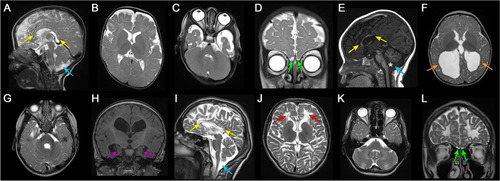

Neuroimaging findings of individuals with OGDHL pathogenic variants. Brain MRI findings of individual 1 (A-D), 6 (EH), and 7 (I-L). Sagittal T2 (A and I) and T1 (E) weighted images showed markedly hypoplastic corpus callosum in individual 1 (A) and 7 (I) and dysplastic corpus callosum in individual 6 (E) with hypoplastic rostrum, genu, and anterior body and absent posterior body and splenium (yellow arrows). Mega cisterna magna was present in all affected individuals (A, E, and I, blue arrows), and individual 6 also had inferior vermian hypoplasia and widening of the foramen of Magendie (E, asterisk). Axial T2-weighted images (B, C, F, G, J, and K) revealed varying degrees of diffuse white matter volume loss, most severe in individual 6 (F and G) and 7 (J and K). Individual 7 also had scattered areas of leukomalacia (J, red arrows) and prominent involvement of brainstem and cerebellar white matter. Individual 6 had ventriculomegaly and colpocephaly (F, orange arrows). Coronal T2 (D and L) and T1 (H) weighted images showed hypoplastic olfactory bulbs in individual 1 (D) and 7 (L) (green arrows) and hypoplastic hippocampi in individual 6 (H, purple arrows)